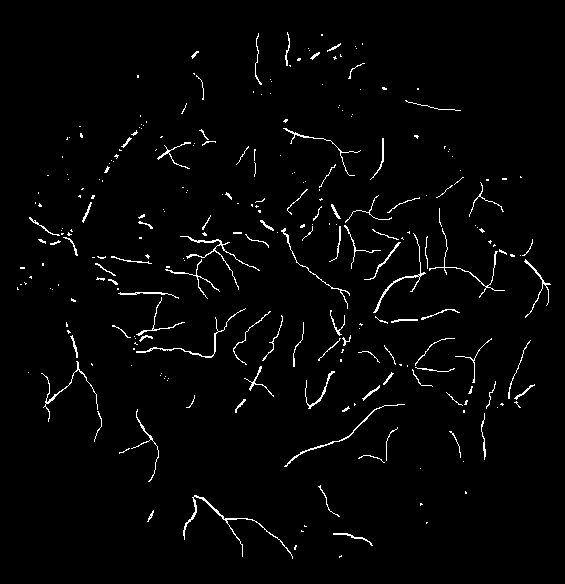

To justify the performance of our model, we compare the 4 metrics with 8 representative previous works from all 3 open-access datasets. The comparison results presented in Table 1 show that our MP-Net model outperforms the state-of-the-art methods regarding accuracy and in all three datasets, which meter the practical prediction quality and the overall prediction quality independent on thresholding specifications. The advancement is greater in the DRIVE dataset. It’s related to the fact that the DRIVE dataset contains more thin vessels, which is the main target of our model. Specificity is also the highest in DRIVE and CHASE_DB1 while sensitivity is highest in STARE. Particularly, our method outperforms ML-UNet [2] and JL-UNet [4] which adopt a different multi-class approach to also especially tackle the thin-vessels challenge. Figure 2 shows an example of our segmentation maps on DRIVE. As can be seen, most thin vessels and boundary areas have been meticulously picked up.